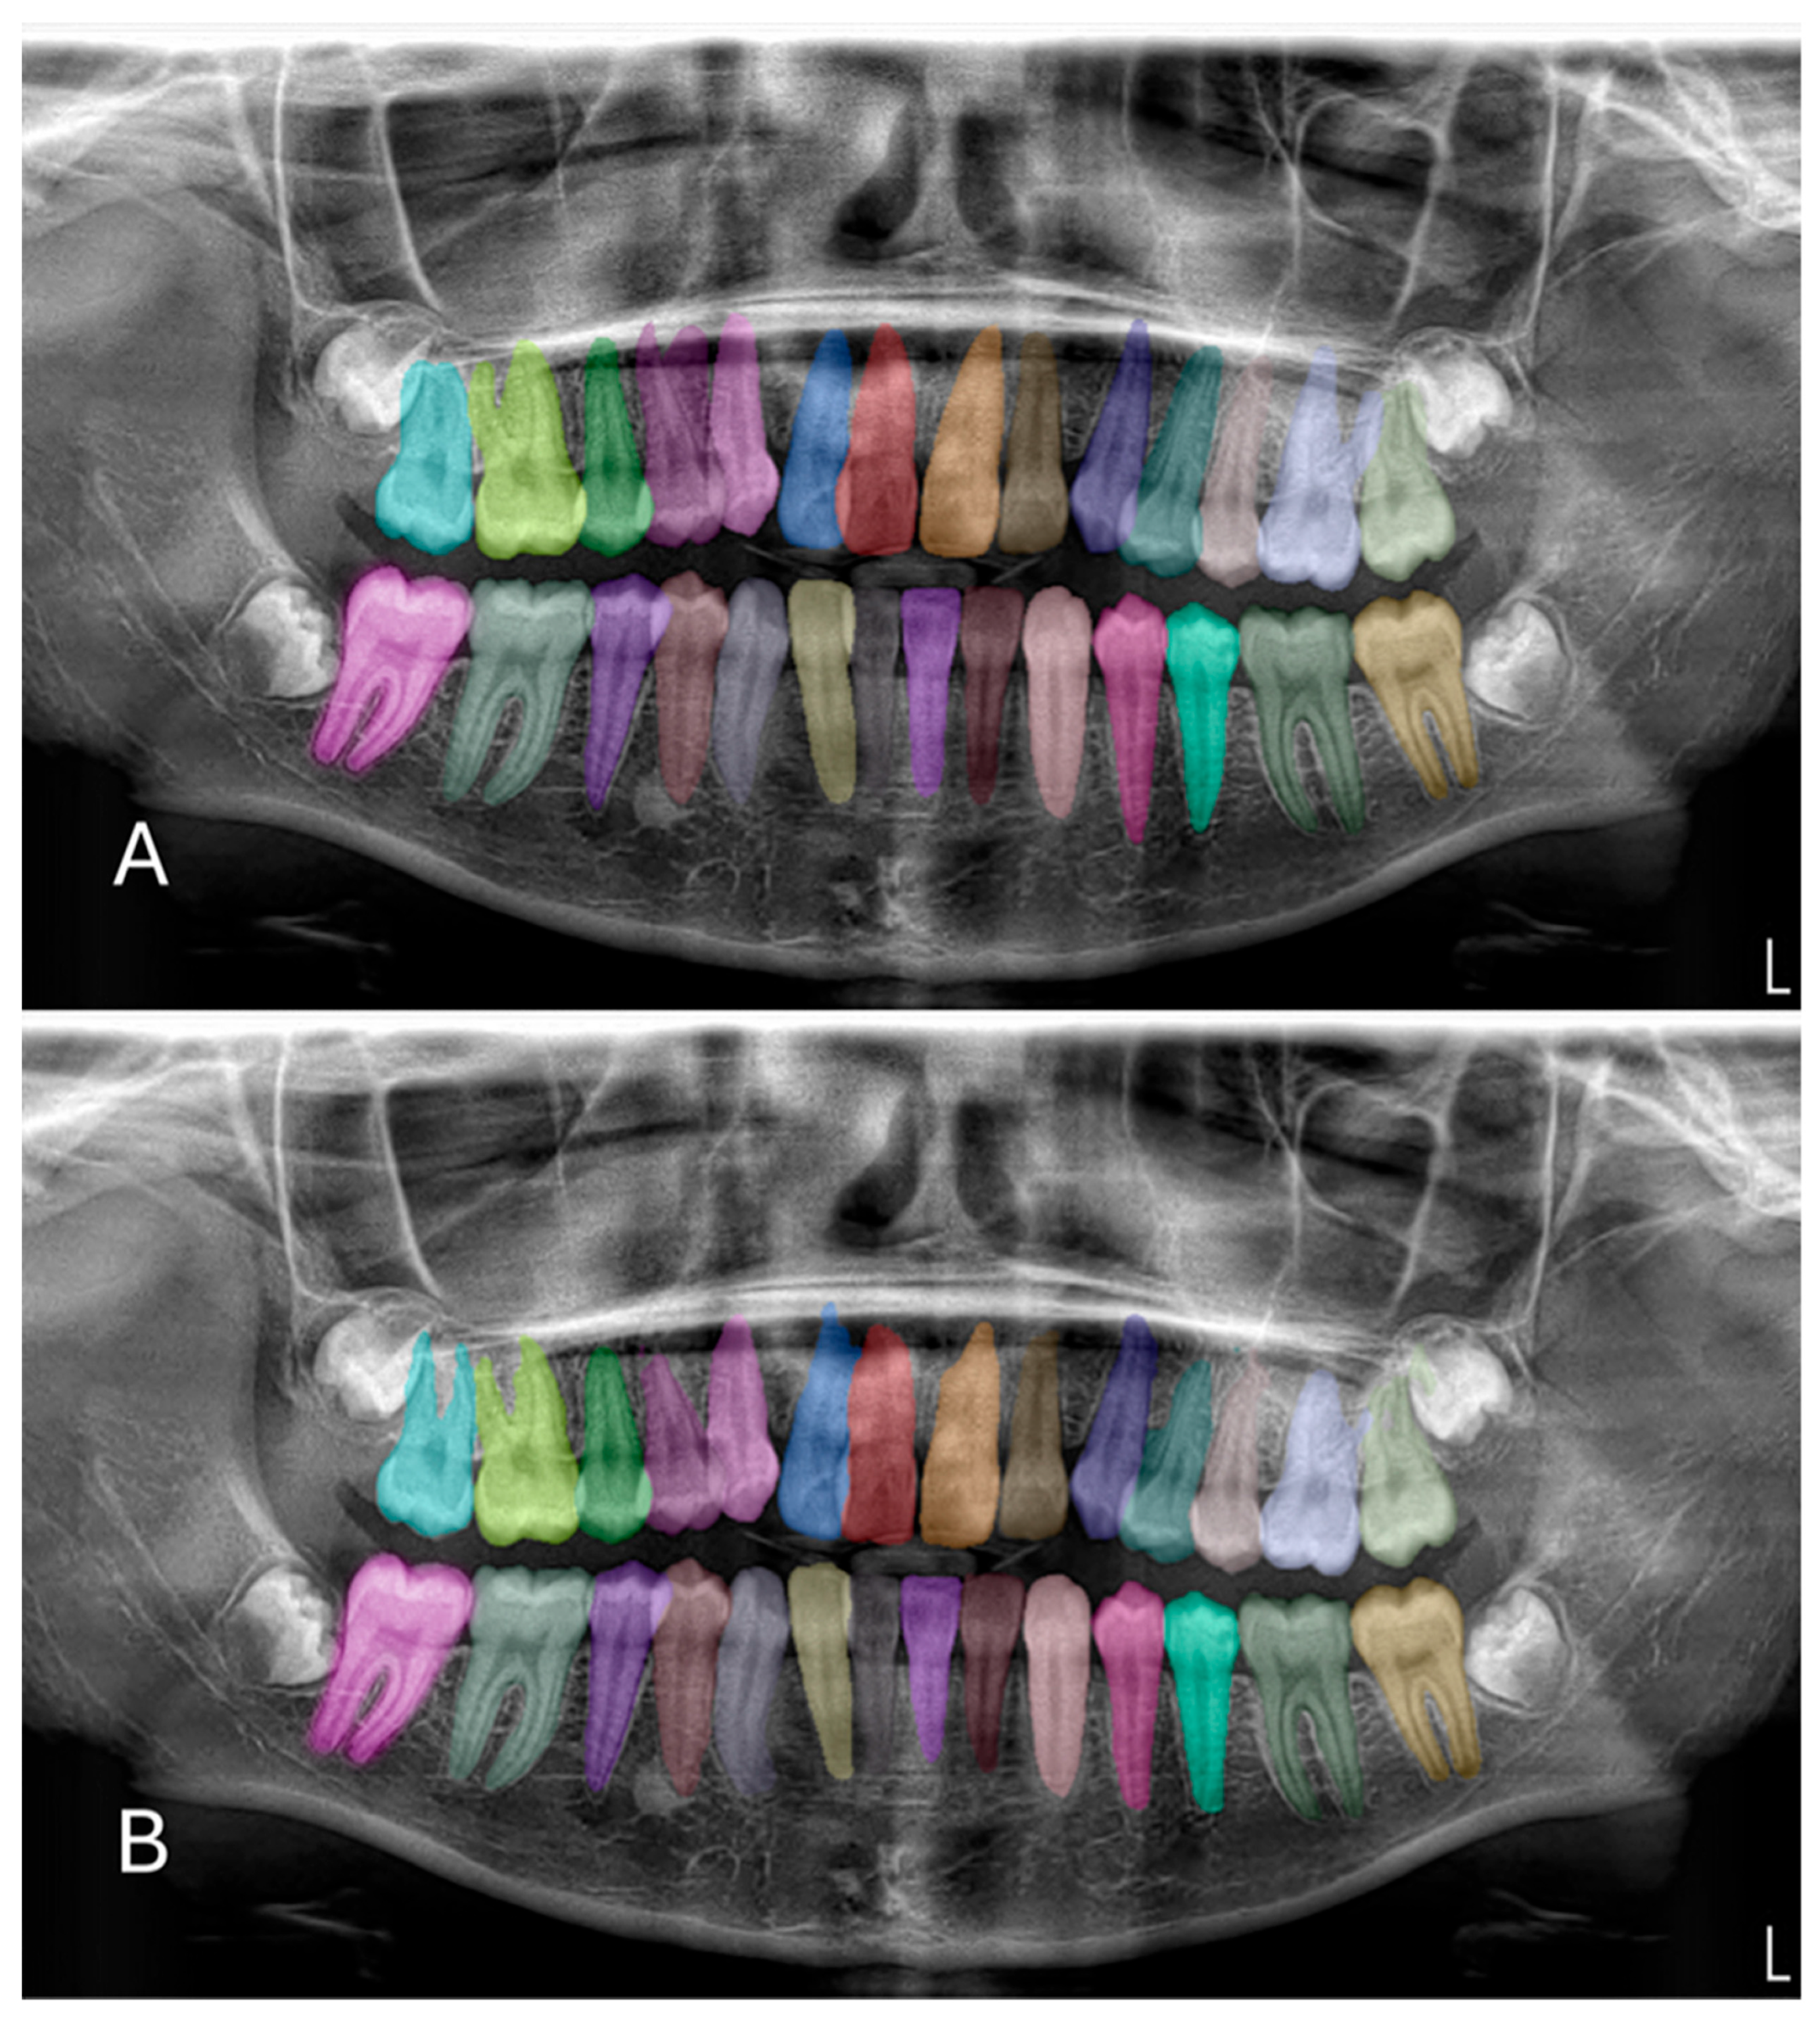

In the test phase, the U-Net-based deep learning model demonstrated robust segmentation and classification performance of primary and permanent teeth in panoramic radiographs. The Dice similarity coefficient (DSC) was 0.8773, indicating a substantial overlap between the model’s predicted segmentations and the ground-truth annotations (Figure 2 and Figure 3). Concurrently, the intersection over union (IoU) score of 0.8125 reflected the model’s ability to precisely localize target structures. Further supporting its robustness, the model achieved a precision of 0.9115 and a recall of 0.8974, leading to an F1 score of 0.9027. Collectively, these metrics confirm the model’s capacity to accurately delineate teeth while maintaining a balanced trade-off between false positives and false negatives. During the validation phase, the model maintained a high accuracy of 96.71%, indicating consistent performance across a variety of panoramic radiographs. Although the validation DSC (0.8062) and IoU (0.6936) were slightly lower than the test phase metrics—possibly due to dataset variability—the values remained indicative of reliable segmentation. Additionally, the validation loss was recorded at 0.2571, which falls within an acceptable error range for this type of segmentation task. Notably, the peak validation DSC reached 0.8540, while the highest IoU was 0.7556, suggesting that the model shows potential for further refinement.

Figure 2. Example images demonstrating the performance for segmentation of permanent teeth on panoramic radiographs between manual annotation by researchers and U-Net based artificial intelligence (AI)-predicted label masks. (A) Manual segmentation performed by clinicians. (B) Automatic segmentation by the model. In the segmentation figures, each tooth is represented with a distinct colour to visually differentiate regions; however, the model treated all teeth as unified segmentation classes during training.